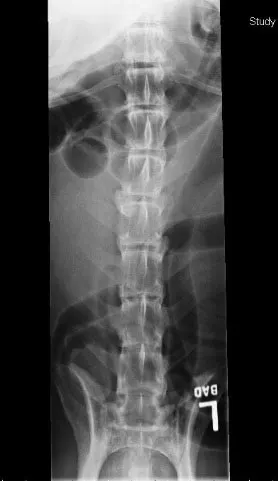

Spondyloarthropathy is diagnosed radiographically by the presence of bony proliferation, sclerotic margins, and osteophytosis of the articular facets, and is not necessarily associated with ventral spondylosis deformans. Osteochondritis dissecans lesions or congenital hypoplasia of the articular facets (arrows) can also be seen in young dogs; although not commonly diagnosed, these findings (which can lead to spondyloarthropathy) may be underrecognized in patients that do not undergo advanced imaging studies. Myelography, computed tomography, or magnetic resonance imaging is indicated to determine if bony proliferation due to degenerative joint disease is causing spinal compression.

Spondyloarthropathy (or osteoarthropathy) in dogs is a degenerative, age-related process involving the articular facets (click on PDF icon at the top to see the images with arrows). Performance animals may have pain and inflam­mation associated with these degenerative changes, but many dogs show no clinical signs. Treatment is similar to that used for arthritis of the appendicular skeleton.